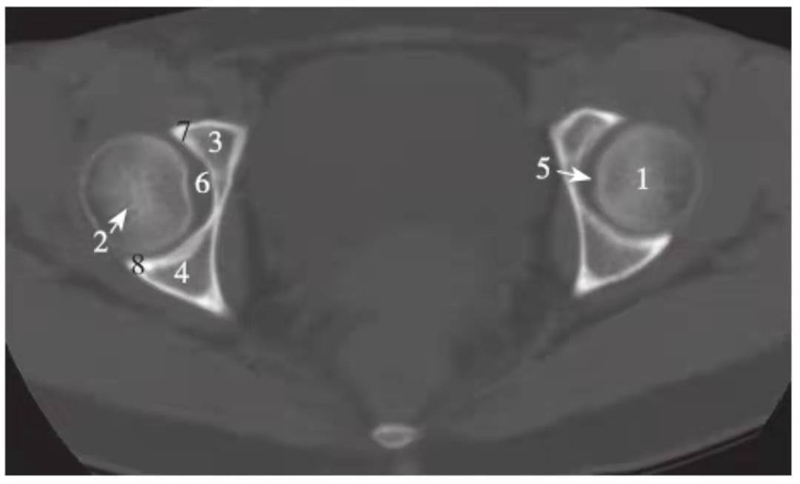

图3 股骨头凹层面(骨窗)

1.股骨头;2.星芒状结构;3.耻骨;4.坐骨;5.股骨头凹;6.髋臼窝;7.髋臼前唇;8.髋臼后唇